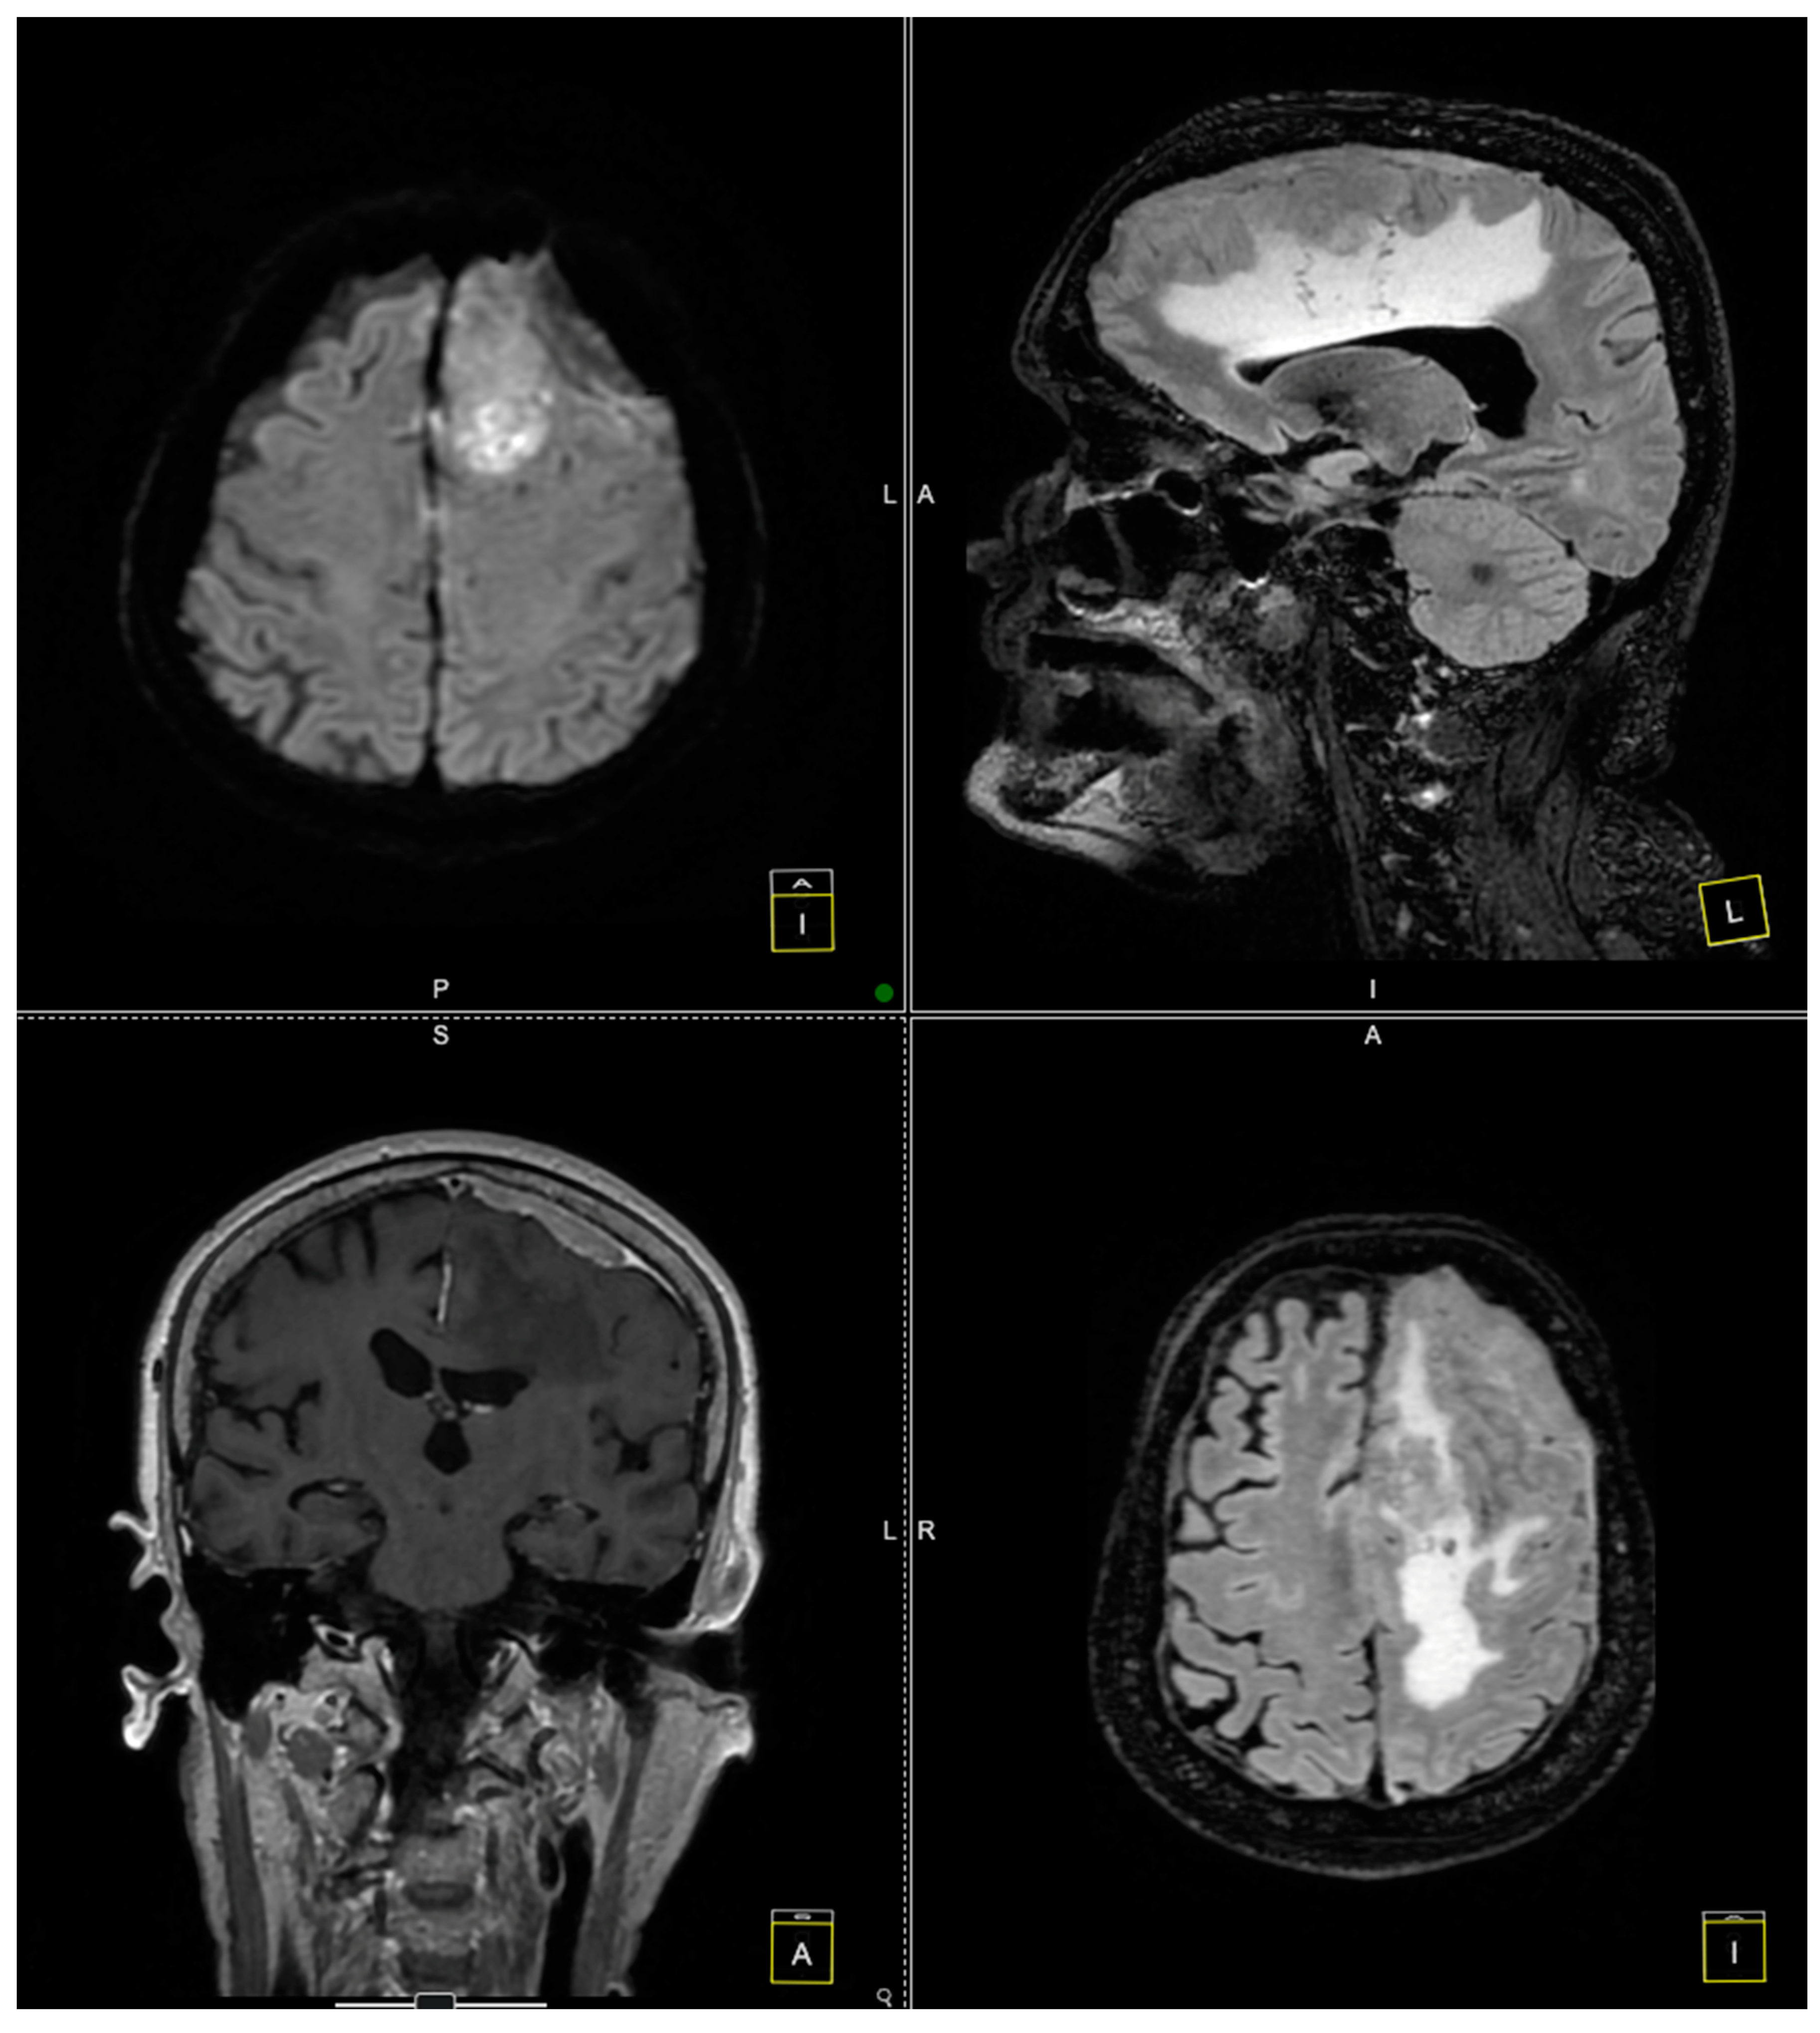

2. Case Presentation